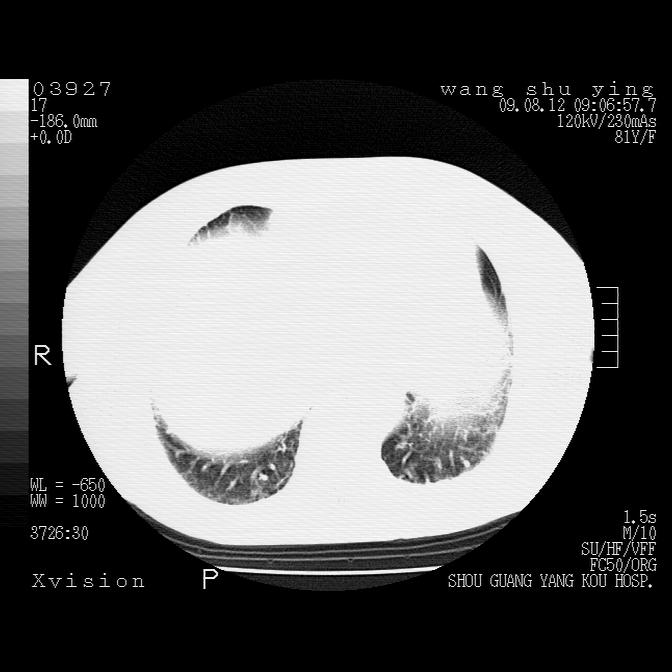

以下是引用帅河马在2009-8-12 12:59:00的发言:[br]两肺感染性病变伴双侧胸膜肥厚。[br]左侧甲状腺腺瘤不除外。[br]腹水+心包积液。[br][br][本贴已被 帅河马 于 2009-8-12 13:14:32 修改过]

以下是引用sdzyy在2009-8-12 18:17:00的发言:[br]两肺感染性病变伴双侧胸膜肥厚。[br]左侧甲状腺腺瘤不除外。[br]腹水+心包积液。[br]支持

以下是引用随光逐影在2009-8-12 19:42:00的发言:[br]1)两肺感染性病变伴双侧胸膜肥厚。2)不排除左侧甲状腺腺瘤。3)肝脏占位性病变;建议行进一步检查。